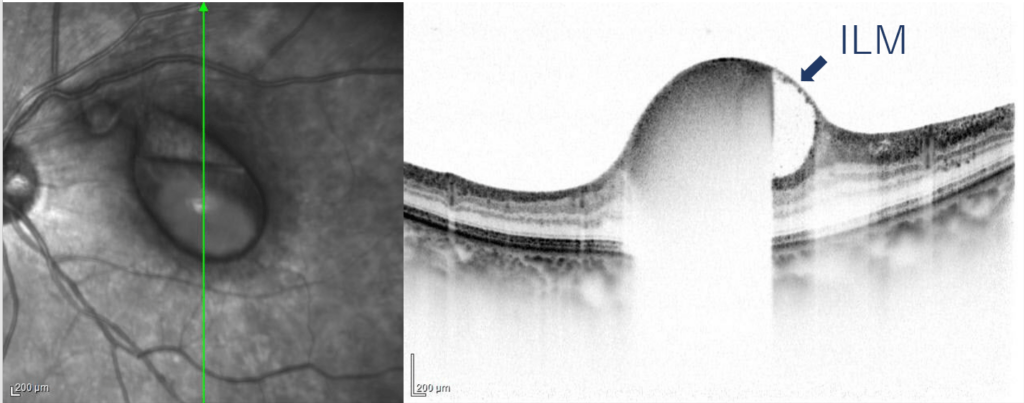

中心窩を含む鏡面形成を伴う出血がみられる。その鼻側上方に白色隆起性病変がみられる

内境界膜下 subinternal limiting membraneに出血がみられる